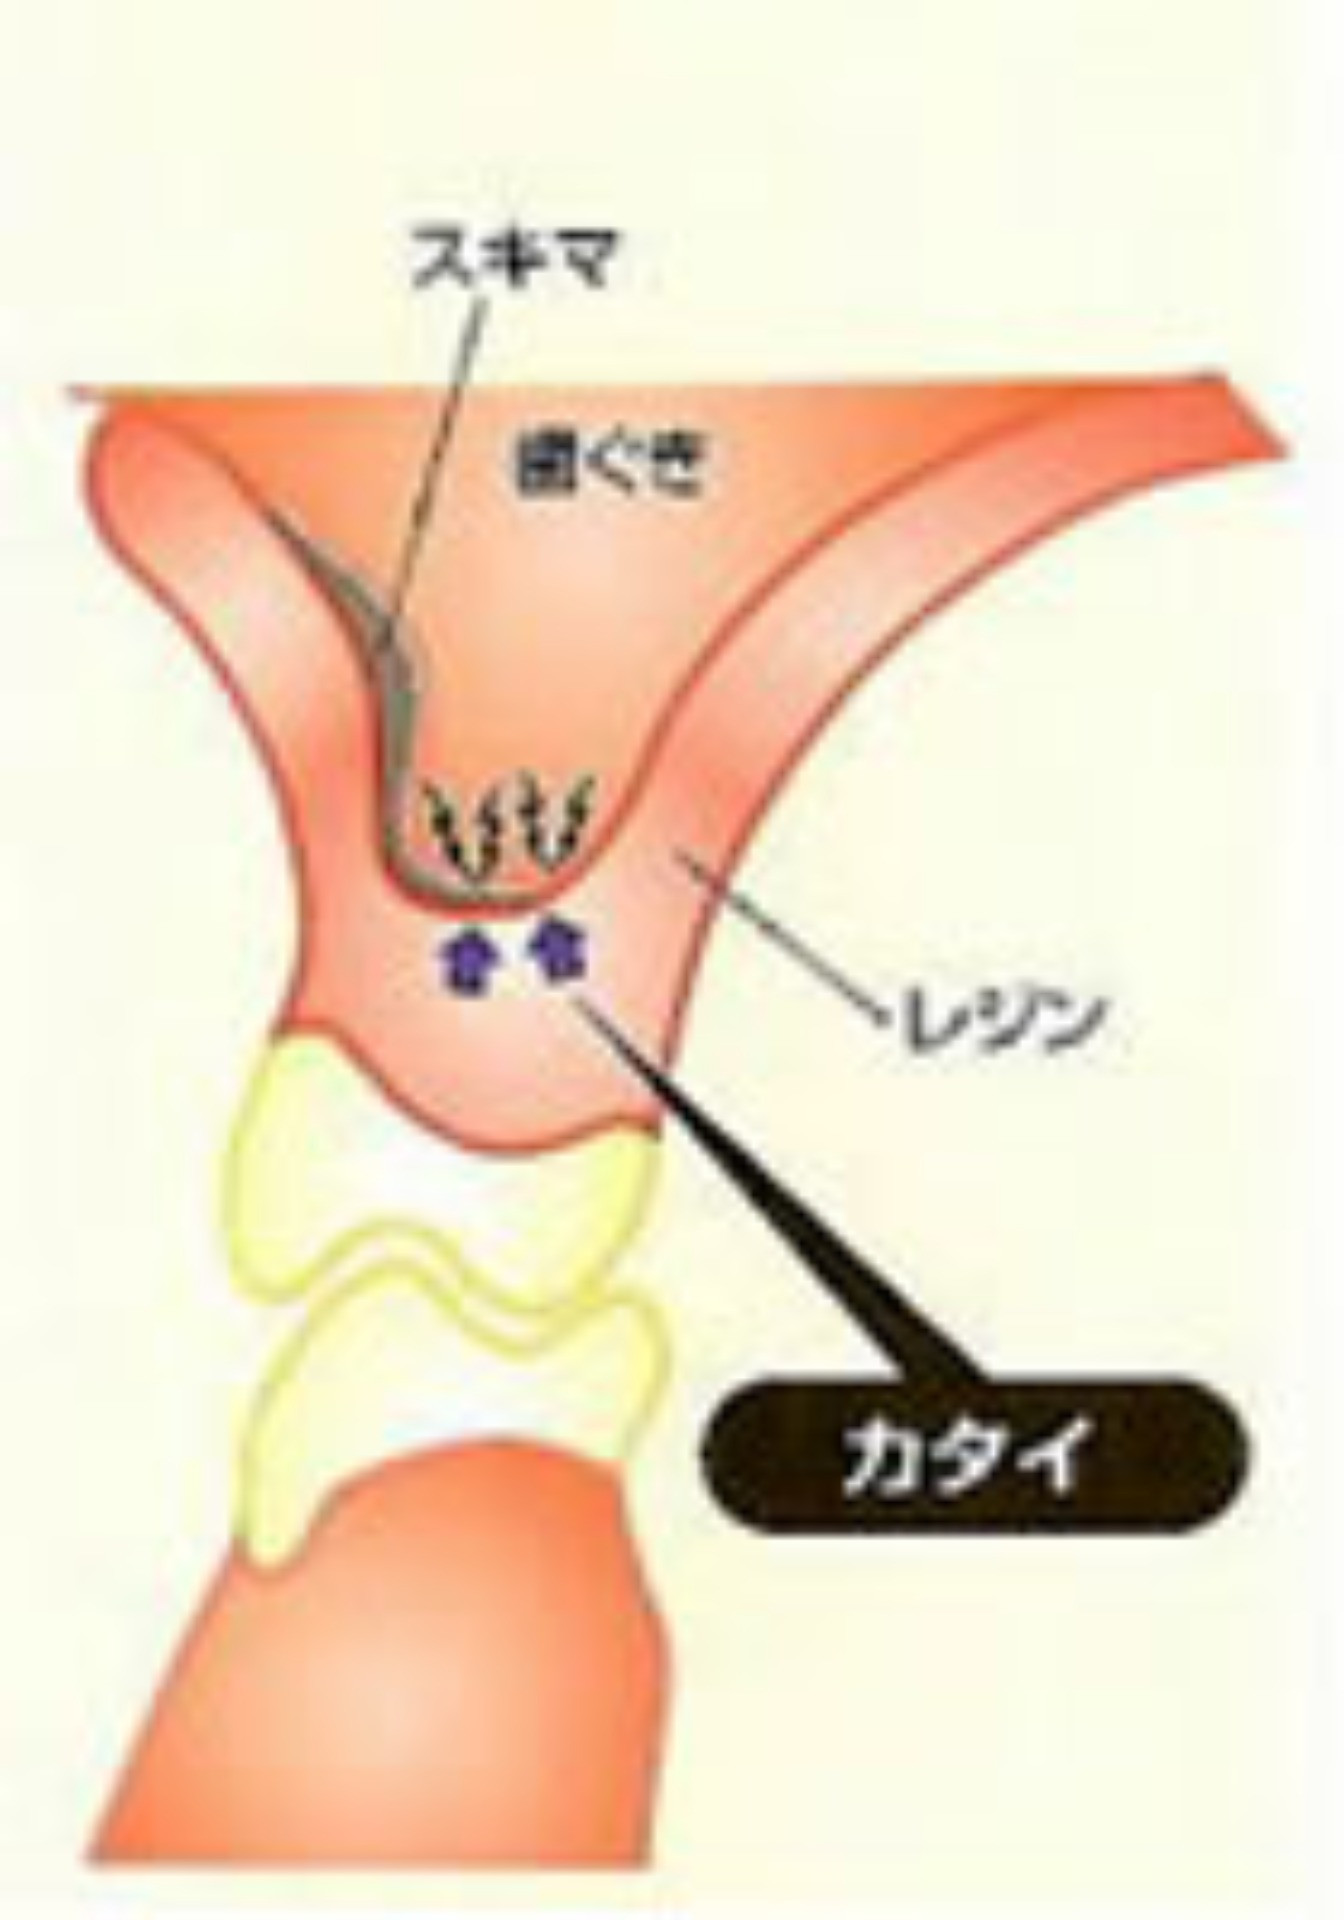

ソフトデンチャーとは、義歯の内面に、やわらかい生体用バイオシリコンを使用しており、歯茎や歯にぴったりと合い、隙間が少ない為、食べかすがはさまりにくく、バイオシリコンで安定させるため、金具の見えないタイプの義歯も可能です。

ソフトデンチャーは歯ぐきに接触する面に特殊加工を施した入れ歯です。弾力性のある軟性樹脂(シリコン状の素材)を使用しているため歯ぐきに加わる負担を軽減させ痛みを感じません。 |

体温により軟化し歯ぐきに吸い付きます。顎の骨が薄くなった方や入れ歯が合わない方にお勧めいたします。 |